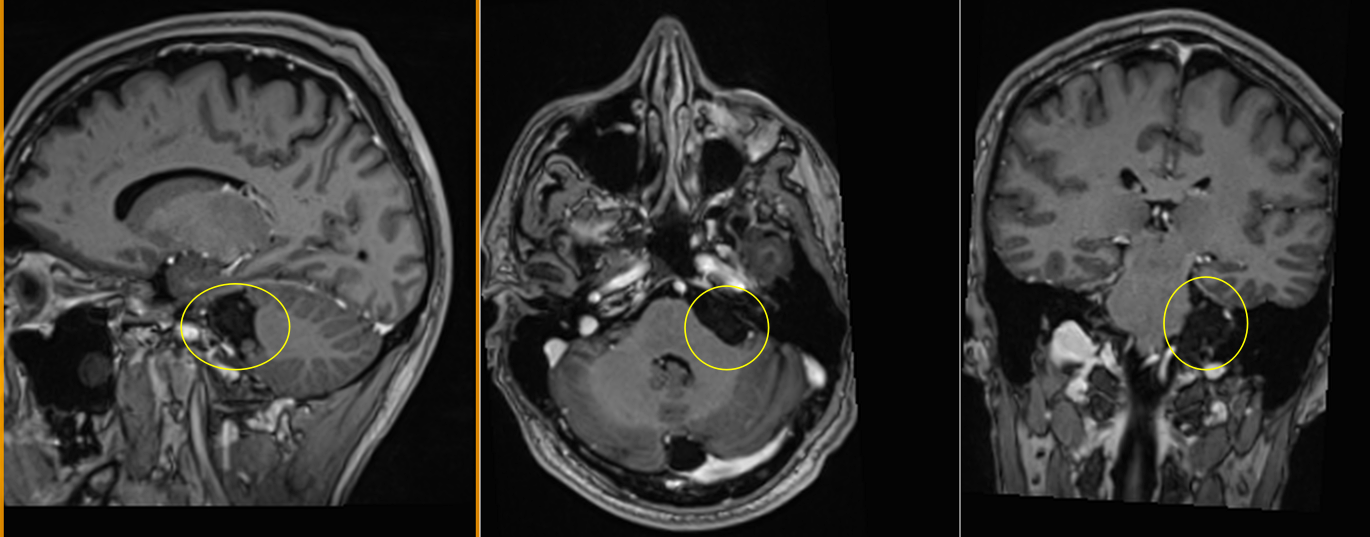

Imagistica prin rezonanță magnetică (IRM):

- Investigația de elecție.

- Chisturile epidermoide:

- Hiposemnal T1, hipersemnal T2.

- Nu se încarcă cu substanță de contrast.

- Apare restricție de difuzie pe secvențele DWI – caracteristică importantă.

- Chisturile dermoide:

- Hipersemnal pe T1 (datorită conținutului lipidic).

- Semnal mixt pe T2.

- Poate avea semnal susceptibil pe secvențe GRE dacă există componente calcificate.

- Poate fi evidentă o fistulă cu exteriorul.

Chisturile epidermoide:

- Unghiul ponto-cerebelos (cel mai frecvent).

- Cisterna interpedunculară.

- Cisterna prepontină.